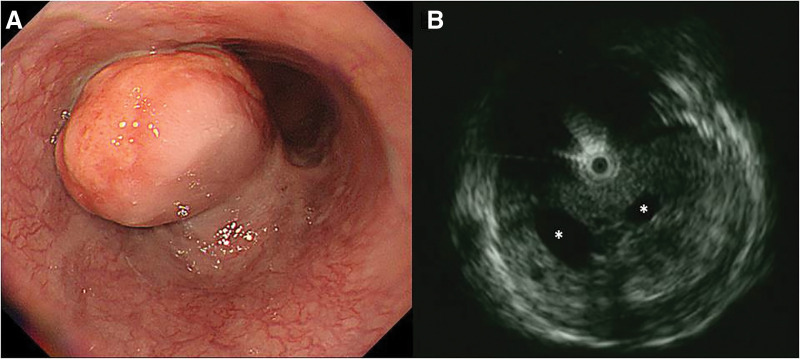

Case presentation: A 77-year-old man presented with epigastric pain. Upper gastrointestinal endoscopy revealed an esophageal mass, prompting referral to our hospital. Endoscopic ultrasonography (EUS) identified a hypoechoic submucosal tumor with multiple cystic components in the lower esophagus. However, EUS-guided fine-needle aspiration (EUS-FNA) did not yield a definitive diagnosis. CT scan demonstrated a 60-mm space-occupying lesion (SOL) in the lower thoracic esophagus with peripheral contrast enhancement and a central low-density area. MRI revealed a SOL in the lower esophagus with high signal intensity on T2-weighted images and moderate signal intensity on T1-weighted images. The lesion contained cystic components exhibiting high T2 and low T1 signal intensities. FDG-PET/CT revealed intense FDG uptake, increasing from maximum standardized uptake value (SUVmax) 11 to 18 over time. Given the large size of the tumor, symptomatology, and inability to exclude malignancy-particularly high-risk gastrointestinal stromal tumor-surgical resection was performed. Laparoscopic esophagectomy was conducted using intraoperative endoscopy for tumor identification. The esophagus was transected proximally using a linear stapler, followed by extracorporeal gastric conduit reconstruction and the overlap technique was used to perform an esophagogastric anastomosis. Postoperatively, anastomotic leakage was detected on day 3, requiring emergency reoperation. The leak had resolved by POD 26, and the patient was discharged on day 48 after the second surgery (day 51 after the initial surgery). Histopathological examination revealed multiple cysts of varying sizes within the lamina propria, lined by columnar epithelium, with no evidence of malignancy. The final diagnosis was esophageal retention cyst.